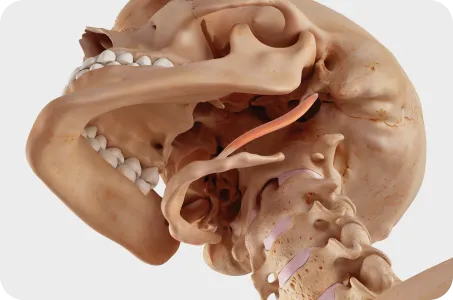

턱관절은 목뼈 1,2번 및 두개골과 함께 움직이기 때문에 턱관절에 문제가 생기면 목뼈과 두개골은 함께 틀어지게 됩니다.

따라서 턱관절 교정시 추나요법과 두개천골요법을 이용하여 목뼈 1,2번과 후두골, 측두골, 나비뼈를 동시에 교정하는 것이 치료효과를 높이고 재발률을 감소시키므로 한의학 치료가 꼭 필요합니다.

두개골 + 턱관절 + 상부 경추 (목뼈 1, 2번) 교정이 중요합니다.

우리 몸 중 움직임이 가장 많은 턱관절은 상부 경추 (목뼈 1,2번)를 중심축으로 움직입니다.

이 상부 경추가 틀어지면 후두골을 제대로 받치지 못하고, 두개골 또한 점점 틀어져 안면비대칭이 나타나게 됩니다.

턱관절 이상 (뇌로 올라가는 신경과 혈관이 꼬인 상태)이 있으면 목뼈 1번, 2번과 두개골에 이상 (중추신경계 기능저하)을 초래하며 전신의 구조와 기능에 이상을 일으켜 전신질환을 일으킵니다.